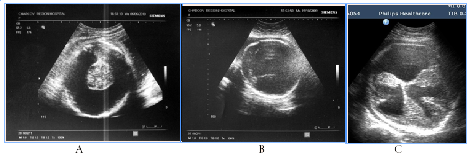

In 5fetuses with severe prolonged course of placental dysfunction we antenatally detected modified insular complex with anomalously broad lateral (Sylvian) sulcus as a signs of abnormal gyration and sulcation (Figure 7). US images of cortical dysplasia in our study were associated with fetal intrauterine growth retardation (IGR), Oligohydramnios, metabolic acidosis and neuro infection. These fetuses had adverse GPO (3cases) and extremely unfavorable CPO (2cases) (Figure 8).

Figure 7NSG of two fetuses of the same gestational age (29 GW) with normal brain image (A), also with a signs of cortical dysplasia (B).

Figure 8Abnormal image of the cerebral cortex as a manifestation of abnormal neuronal migration in two fetuses in 3rd trimester of pregnancy, fetal US and neonatal MRI.

NSG of two fetuses of the same gestational age (29 GW) with normal brain image (A), also with a signs of cortical dysplasia (B).

Figure 8 Abnormal image of the cerebral cortex as a manifestation of abnormal neuronal migration in two fetuses in 3rd trimester of pregnancy, fetal US and neonatal MRI. A, B) 30GW, cortical dysplasia, the type of neuronal heterotopia and pachygyria, long-term violations as severe epilepsy and retardation of development in catamnesis. C,D,E) 29 GW, cortical dysplasia in the fetus with significant IGR and antenatal distress, postnatal transmantian dysplasia, lissencephaly and presilvian polymicrogyria that clinically was accompanied by hypotension and child neurological disabilities.